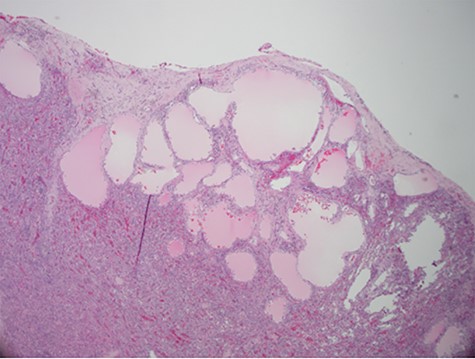

Despite aggressive resuscitation, the patient’s hemodynamics and clinical exam declined. He was taken emergently to the operating room for exploratory laparotomy, evacuation of hemoperitoneum and splenectomy. The spleen was noted to have an isolated nodular, cystic appearing portion in addition to large area of capsular tear. In total, he received four units of PRBC, four units of fresh frozen plasma and one unit of platelets peri-operatively; however, he continued to show signs of hemorrhagic shock. Morning lab-work revealed a Hgb of 5.9 mg/dL from 7.6 mg/dL despite two additional units of PRBC on post-operative day one. Due to continued decline in Hgb and ongoing tachycardia, he returned to the operating room on post-operative days two and four for repeat exploration. Each procedure failed to identify an obvious source of bleeding, except for diffuse oozing in the peritoneal cavity. Further family discussion revealed a history of Hemophilia A in the patient’s brother, diagnosed during childhood. New diagnostic workup was obtained and was consistent with a variant of Hemophilia A. He was subsequently treated with recombinant Factor VIII to a goal of 80–100%, per hematology recommendations, and underwent definitive closure with hemostasis noted on post-operative day six. Pathology report returned as a ruptured spleen with hemorrhage and a subcapsular nodule with dilated lymphovasculature consistent with splenic lymphangioma (Figs 2 and 3).

Hematoxylin and eosin stain photomicrographs from splenectomy consistent with splenic lymphangioma with 10x magnification.

Hematoxylin and eosin stain photomicrographs from splenectomy consistent with splenic lymphangioma with 40x magnification.